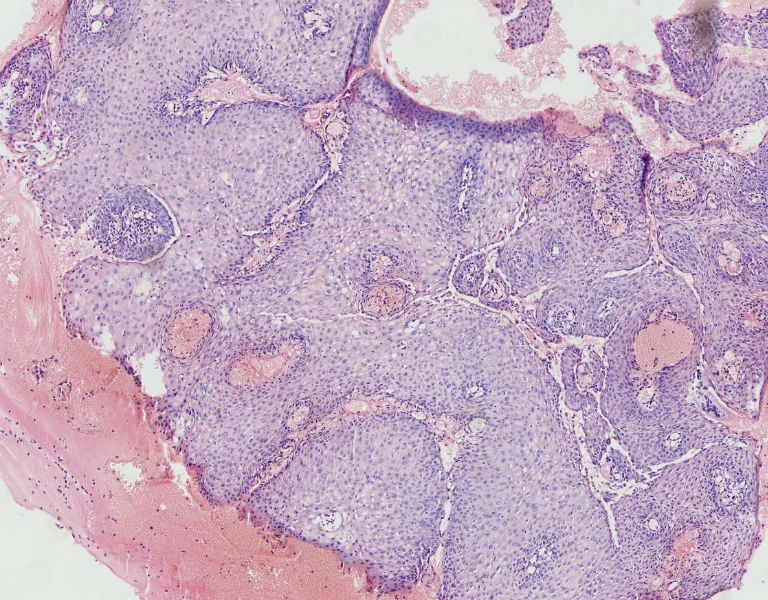

女45岁,宫颈口可见一突出物直径约0.5菜花状质脆

图2

细胞异型性不太大,考虑湿疣样增生

CIN3,伴湿疣感染

细胞异型不大,乳头状瘤。

乳头状的CIN,有平切,似乎有高级别的CIN,需除外癌。